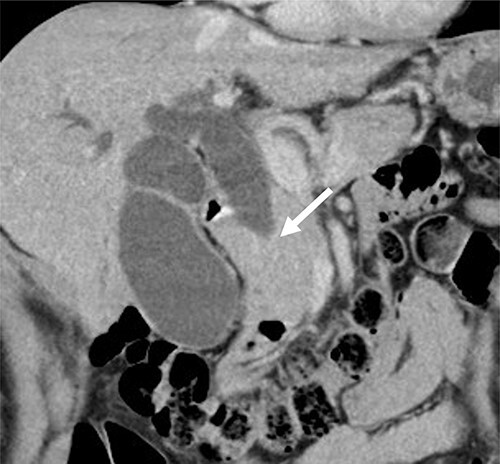

Contrast-enhanced computed tomography (CT) revealed wall thickening and stricture of the distal common bile duct (CBD) (Fig. 1). Dilation of both the intrahepatic bile ducts and the common hepatic duct was also observed (Fig. 2). No lymph node or distant metastases were observed. Endoscopic retrograde cholangiopancreatography revealed irregular stenosis in the distal CBD (Fig. 3). Thereafter, biliary drainage and brush cytology were performed, and an adenocarcinoma was detected.